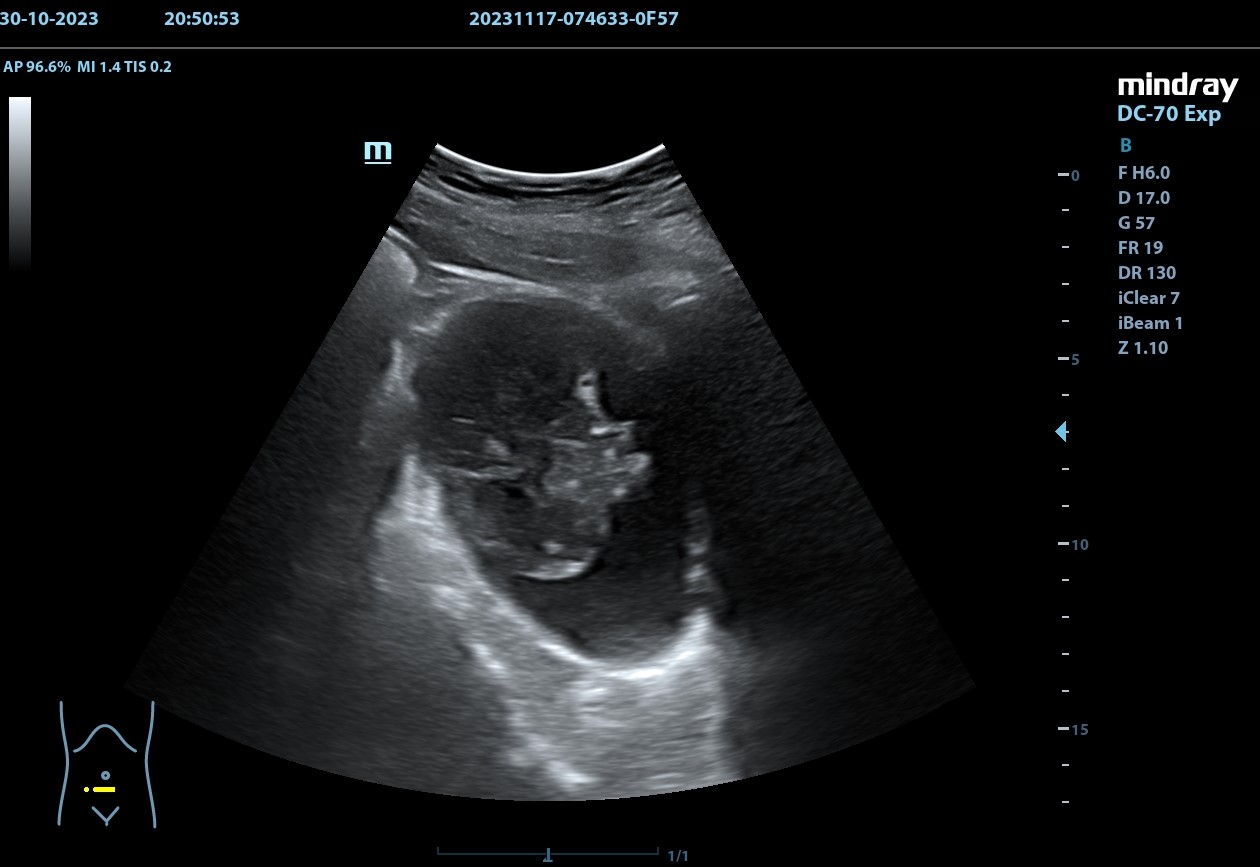

Hallazgos ecográficos

Se realiza, en consulta, una ecografía de las vías urinarias (POCUS), apreciando una lesión excrecente, pediculada, de 7,48 x 6,14 cm, que afecta a la pared izquierda y superior de la vejiga. Doppler negativo. No apreciándose jets ureterales. Riñón izquierdo de 11cm, y derecho de 9.27 cm, sin signos de dilatación de las pelvis renales que sugieran hidronefrosis.

Juicio clínico: Masa intravesical.

Diagnóstico diferencial: Tumor primario epitelial vs. tumor de origen no epitelial.